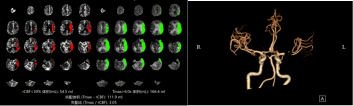

为明确脑梗死的责任血管和梗死周围脑组织血流灌注情况,医生给患者进一步完善了一站式多模CT检查,发现患者左侧大脑中动脉闭塞,左侧大脑半球广泛低灌注。随后神经介入团队立即行动,决定进行急诊介入取栓手术。在这场与时间的较量中,多学科协作无缝对接,从急诊接诊到手术台准备介入取栓,每一步都紧密相连。